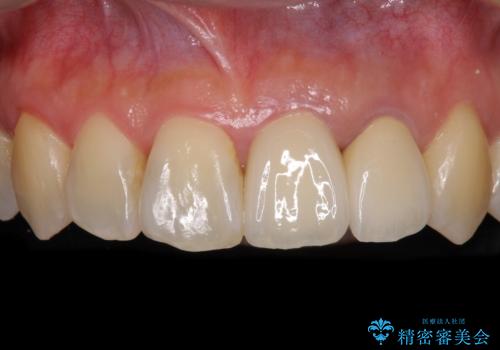

また、上顎前歯と下顎大臼歯に神経を取り除いた歯があったため、矯正治療後に、セラミッククラウンにて補綴することとしました。

矯正治療中に上顎前歯が下顎前歯を乗り越える際は、前歯でしか咬めない状況が続くため、食事など不便を感じましたが、治療後には前歯の痛みもなくなり、安定した咬み合わせとなりました。